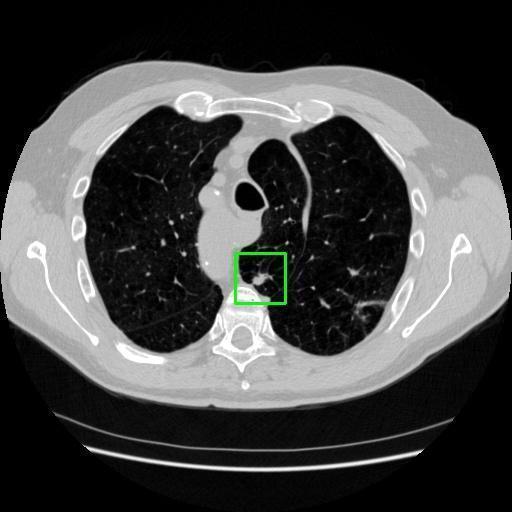

We developed an AI-based system using deep learning models for analyzing lung CT scans to detect and classify pulmonary nodules. We chose the YOLOv11 architecture for its enhanced object detection capability and adapted it specifically for medical imaging, incorporating pixel-level precision and severity classification.

Classification into three severity levels with colored bounding boxes.

Successfully built and deployed an AI model (YOLOv11) capable of detecting lung nodules in CT scans with high accuracy and real-time performance.

Designed a severity classification system that categorizes nodules into null, moderate, and severe using colored bounding boxes, assisting in rapid clinical decision-making.